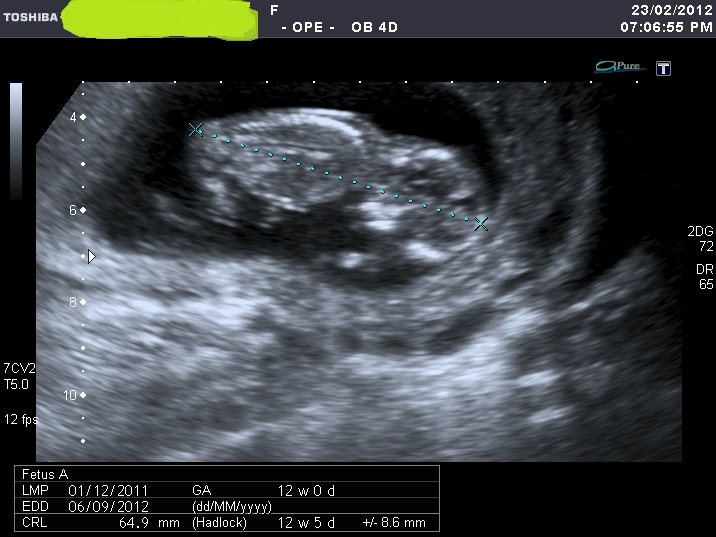

I'm sorry for spaming again with my nub shots, but now when I look at u/s pics I'm not sure I can a see a nub at all????

If you can see it, please enlighten me where to look. Also I think scull looks girly on some pics and boyish on the others.

I was 12 weeks, measuring 12 weeks 5 days